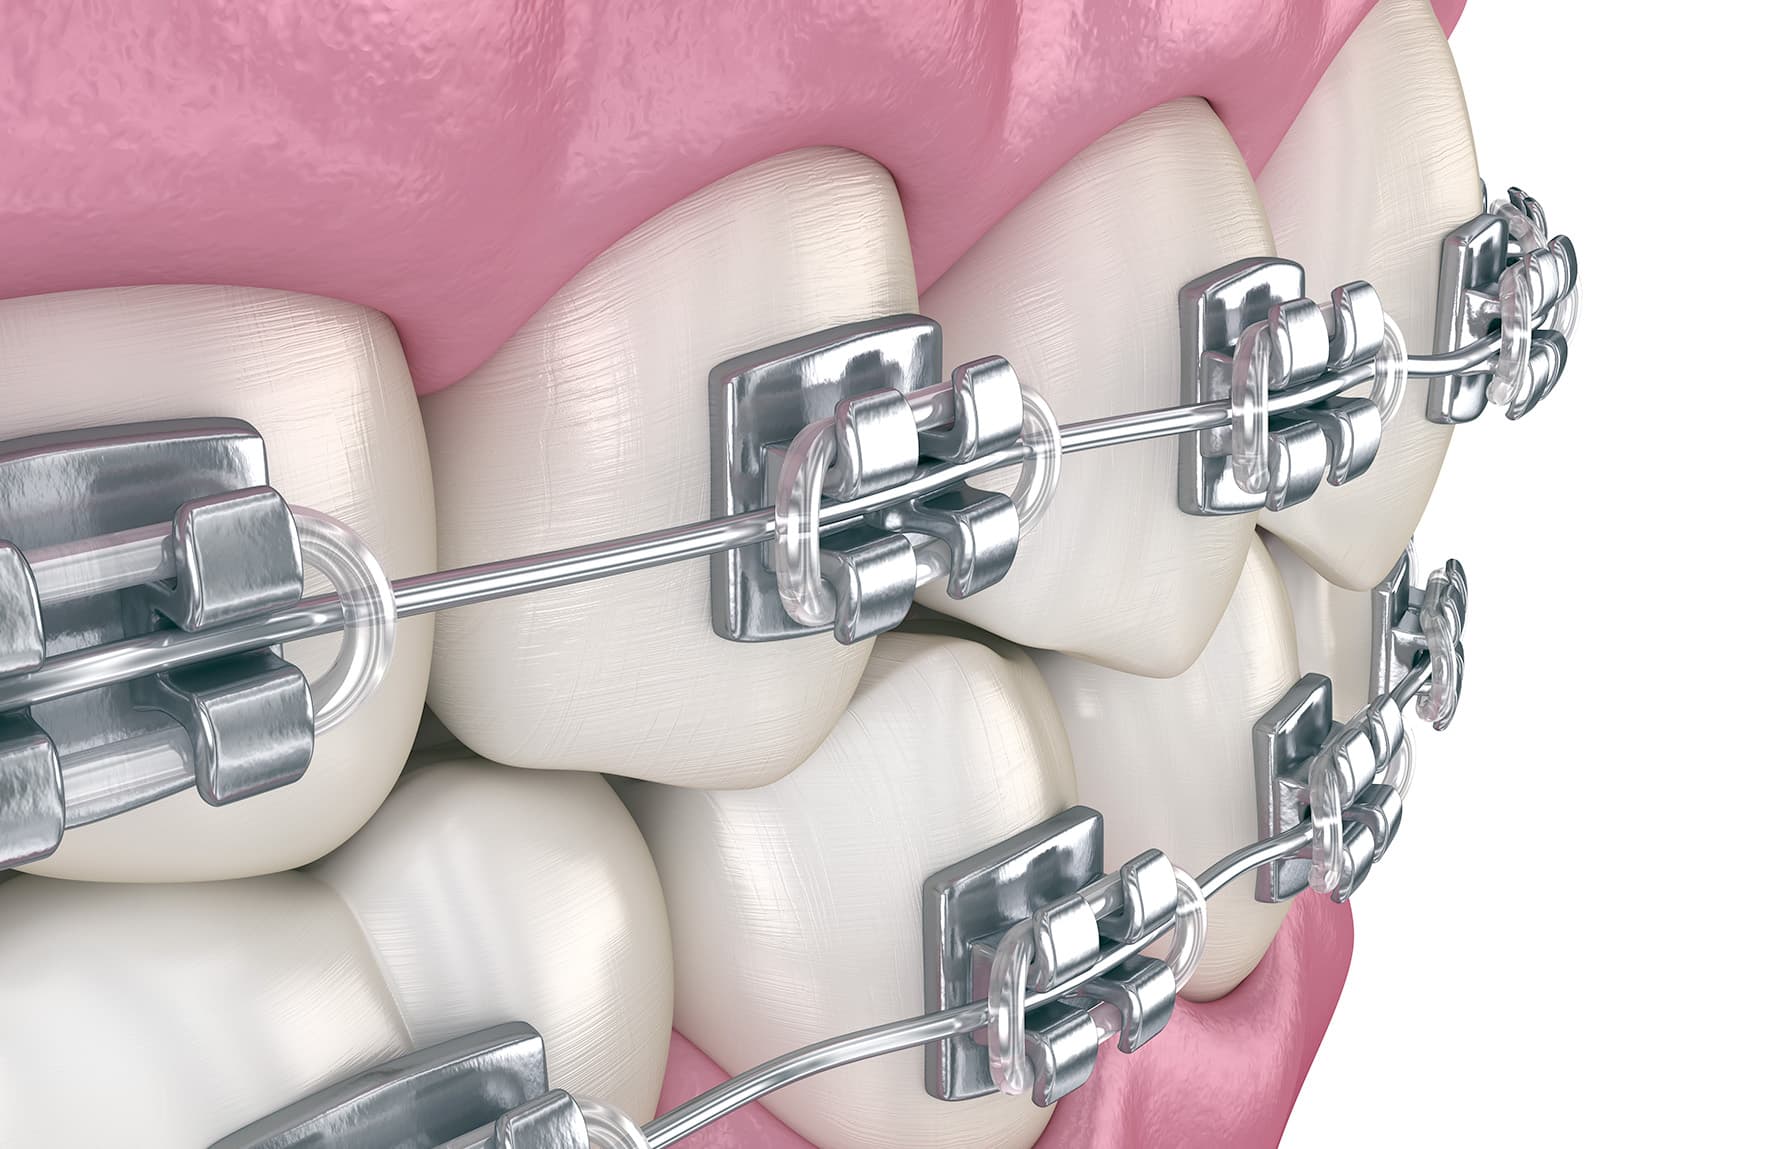

Een beugel corrigeert tanden en kiezen in de goede richting. Het is van belang dat een beugel regelmatig wordt bijgesteld. Op die manier wordt de correctie van de scheefstand optimaal uitgevoerd.